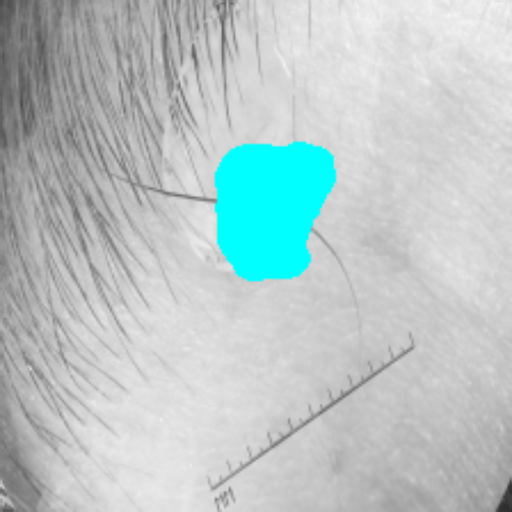

Figure 3 presents a qualitative comparison of segmentation performance on examples from the Synapse, BTCV, ACDC, and ISIC17 datasets. The first two examples (from Synapse) highlight variations in segmentation performance among U-Net, TransUnet, Mamba-Unet, and Swin-Unet. While Swin-Unet performs well in the first example, its performance decreases in the second example, particularly in segmenting the organ highlighted in blue. Additionally, it misclassifies background regions as the class highlighted in orange. In contrast, our approach demonstrates high robustness in segmenting all classes accurately and aligning well with the ground truth masks.

Refer to caption Refer to caption Refer to caption Refer to caption Refer to caption Refer to caption Refer to caption

Slice GT Unet TransUnet Mamba-Unet Swin-UMamba MambaCAFU-V1

Figure 3: Visual comparison of segmentation examples from Synapse (first two examples), BTCV (3-4 examples), ACDC (5th example) and ISIC17 (last example). Columns: input slice, ground truth, Unet, TransUnet, Mamba-Unet, Swin-UMamba, and MambaCAFU-V1.